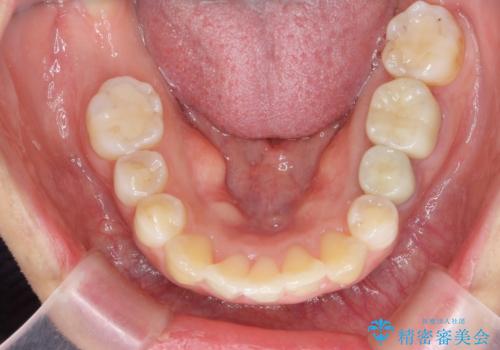

奥歯を後ろに下げて、前歯を並べています。

マウスピースと矯正用のミニスクリューを使用して治療しています。

銀歯も白くということでしたので虫歯治療も一緒に行っています。

右下7は根管治療をおすすめしましたが、患者様のご希望により抜歯となり、そのスペースを利用して下の前歯をならべています。